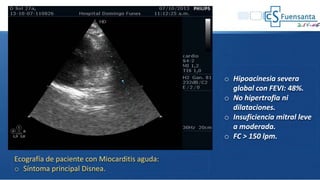

o Hipoacinesia severa

global con FEVI: 48%.

o No hipertrofia ni

dilataciones.

o Insuficiencia mitral leve

a moderada.

o FC > 150 lpm.

Ecografía de paciente con Miocarditis aguda:

o Síntoma principal Disnea.